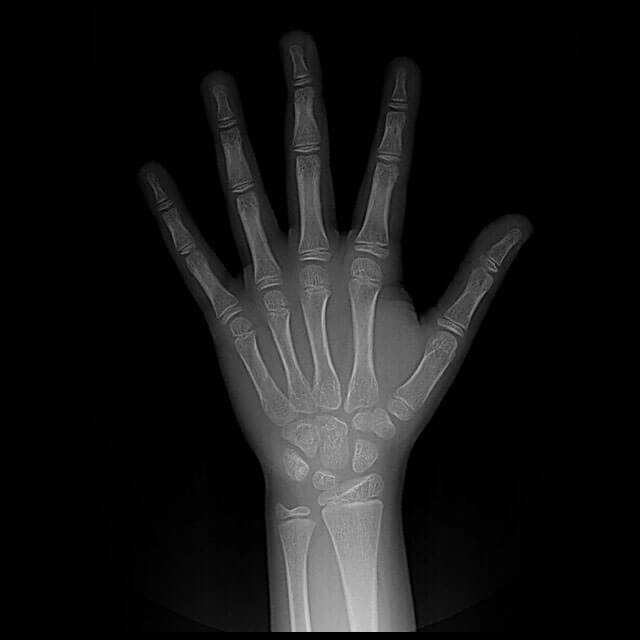

Radiografia Mão e punho(Carpal)

Raio-X de Mãos e Punhos para Idade Óssea é o exame de imagem que analisa os ossos das mãos e punhos para estimar através do amadurecimento dos ossos, a idade de crianças.

A obtenção das imagens é feita com pequenas doses de radiação ionizante. O método não é invasivo e, geralmente, rápido.